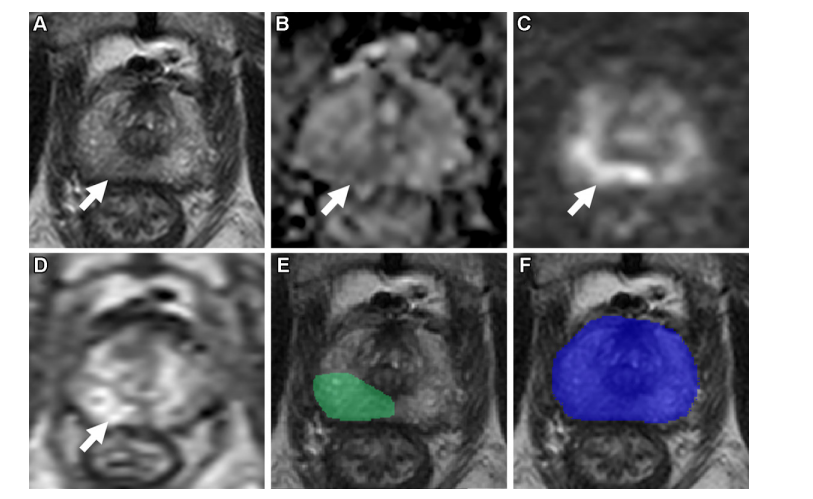

_Figure 6: 在一名74岁男性患者中进行轴向多参数MRI扫描结果:(A)梯度加权图像序列(T2权重)、(B)Alice扩散张量成像(DTI)映射、(C)高b值梯度加权图像(b值=1500 s/mm²)、(D)动态对比增强检查结果(每5.6秒拍摄一次共获得54帧)、(E)梯度加权图像中由 radiologist 综合病变边界线勾画的病变区域、以及(F)梯度加权图像中标记 AI 预测病变区域的预测图谱。(注:在 F 图中无预测到阳性发现;蓝轮廓为 AI 对前列腺解剖结构的预测分割线)。通过显微镜检查发现一例病变样本与 gold standard 匹配。该病变位于右侧上部轴突后方侧位,在第ⅡⅢ胸椎后方段并被归类为前列腺报告分类系统(Prostate Imaging Reporting and Data System, PIRS)IIIc类病灶。值得注意的是,在本研究中该病变未能被 AI 算法检测到而被认为是假阴性发现。从病变取样的 Gleason 分数为7分(3+4),提示为 Gleason 等级7分的前列腺腺癌组织学特征。

图6: 一位74岁的男性患者接受了轴向多参数MRI扫描检查:(A) T2加权回声图谱显示前列腺组织特征;(B) 表观扩散系数B0映象反映细胞迁移能力;(C) 高b值扩散加权图像(b = 1500 sec/mm²)揭示肿瘤微环境特征;(D) 动态对比增强序列第16帧捕捉病变动态过程;(E) 前列腺区域明确边界在PI-RADS分类中确定;(F) AI预测区域未能识别病变边界。放射科医生确认存在一个约1.9厘米的病灶位于右侧顶端腺体外围上部区域,并将其归入PI-RADS分类标准中的第4类:显性假阳性病变。经靶向活检病理学分析证实该病变具有 Gleason分层为7级(3+4),显示为前列腺腺癌病变。然而该病变未被人工智能预测系统识别为阳性病例,并标记为假阴性结果